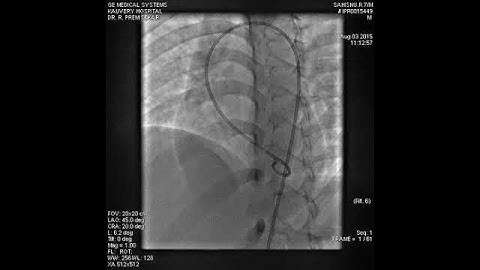

Ventricular Septal Defect after a Starflex device closure